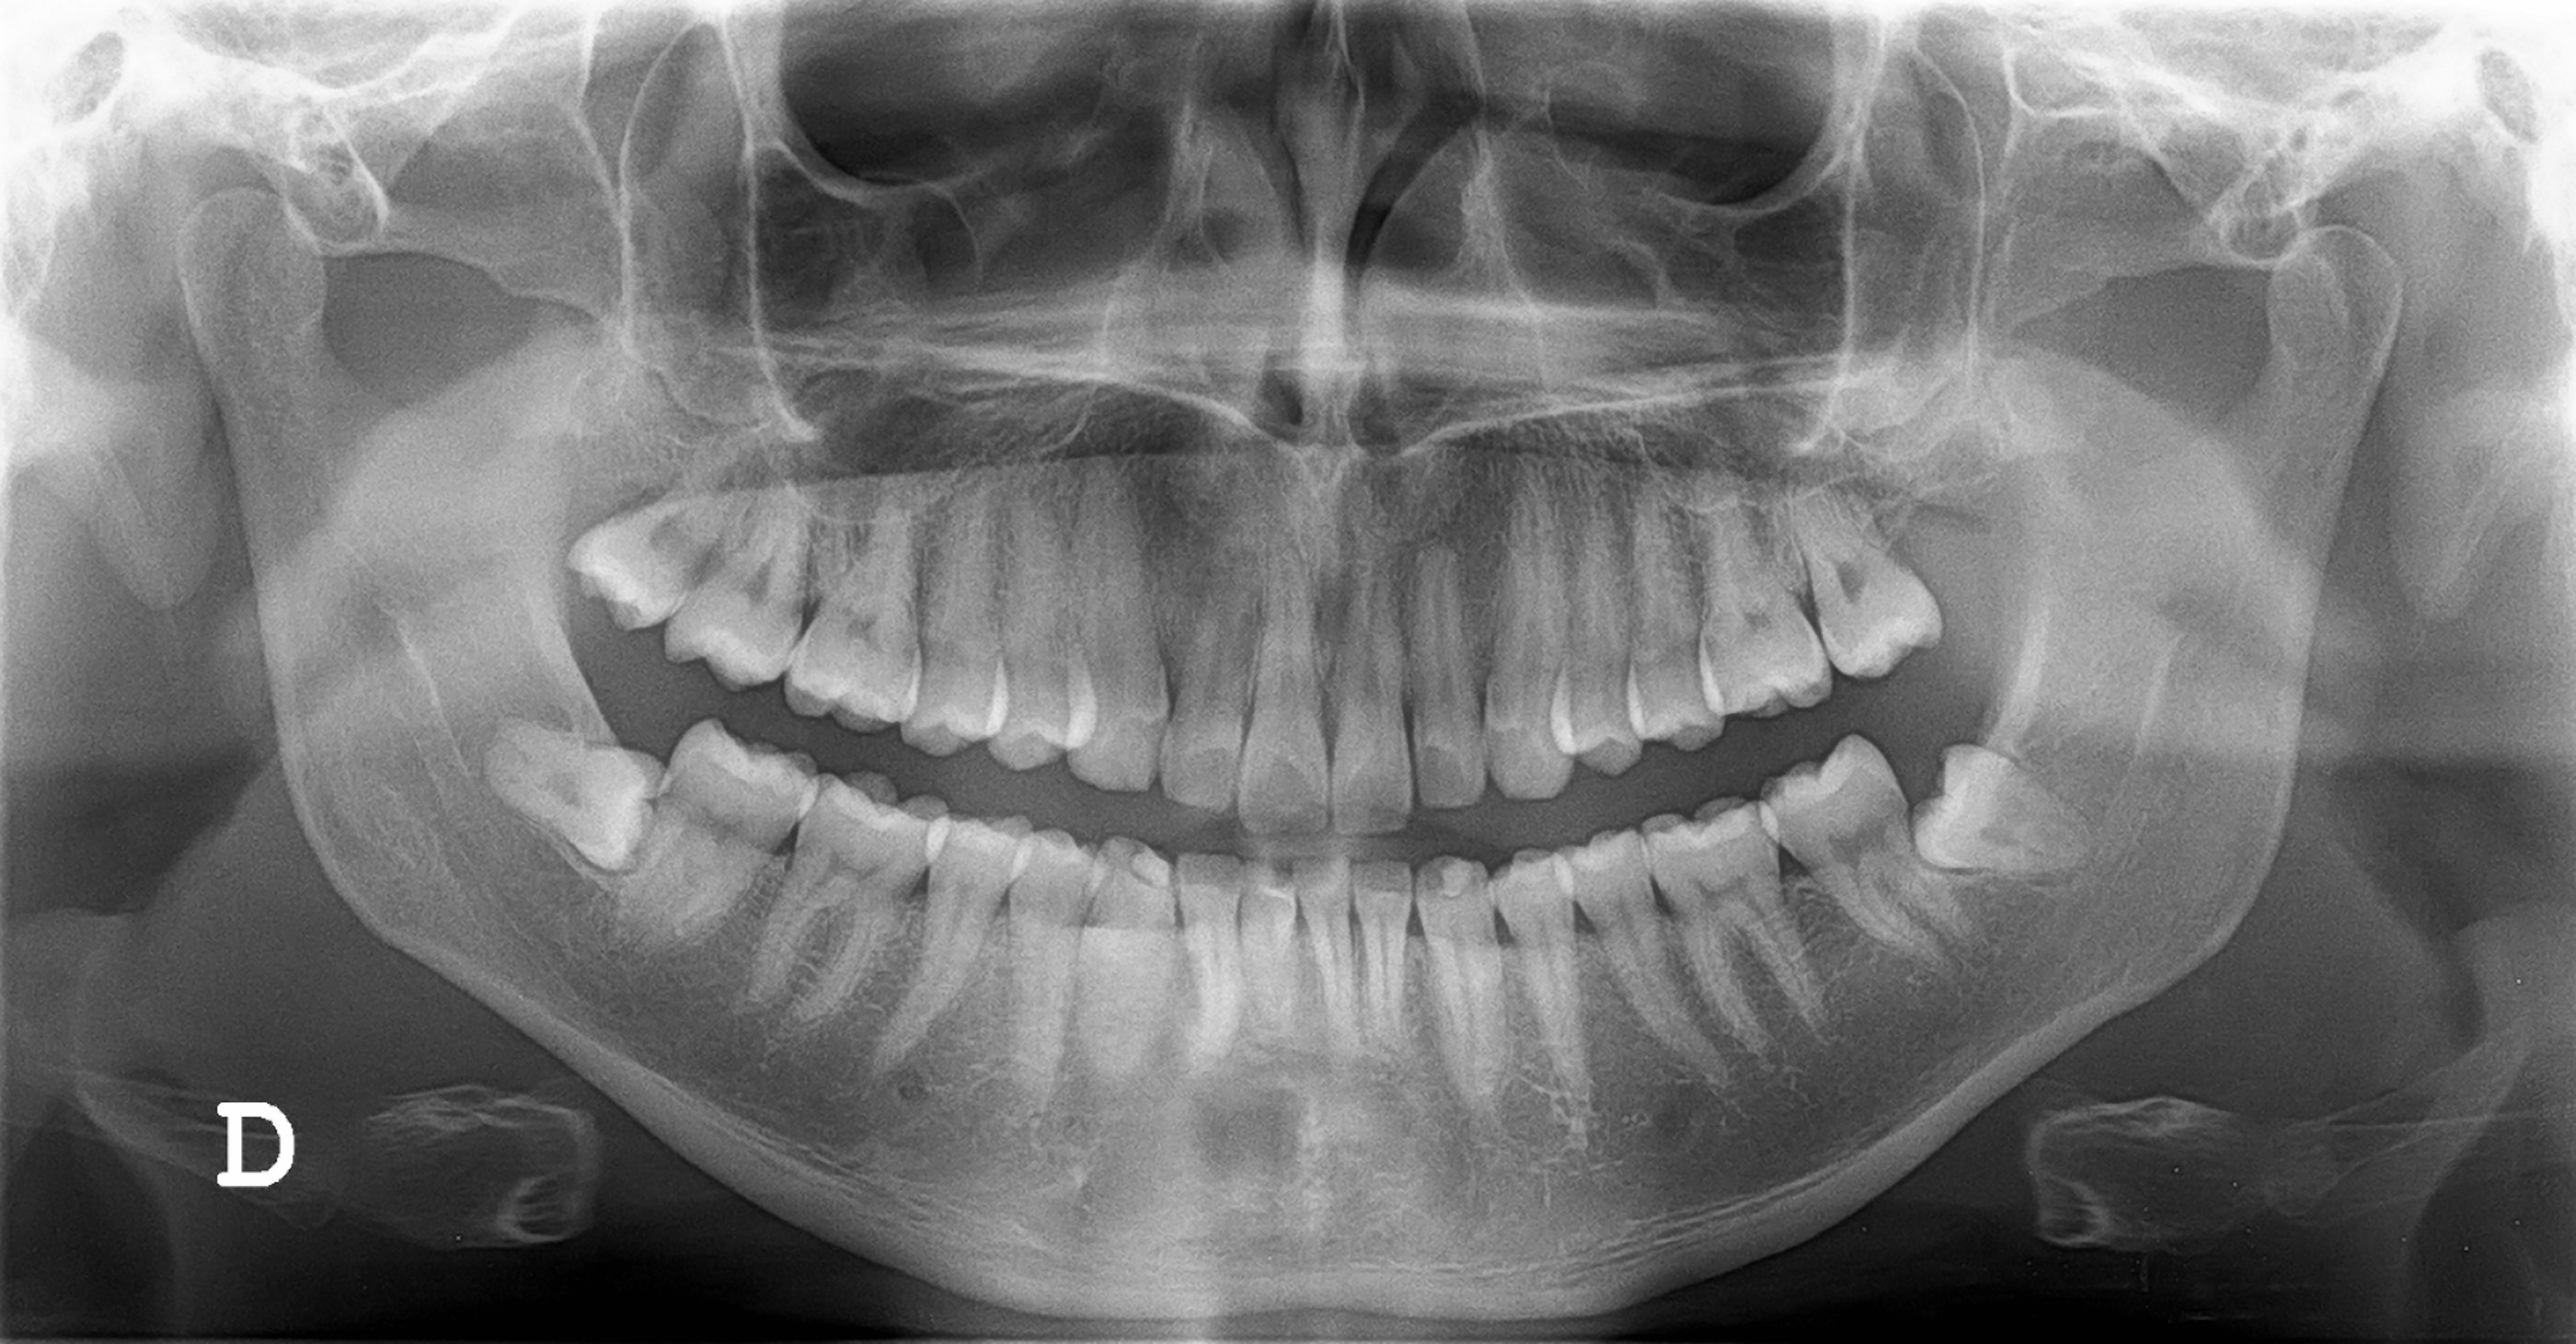

2. Røntgenbilder:

Ved behov tas røntgenbilder for å avdekke skjulte problemer som ikke er synlige ved en visuell undersøkelse.

På en undersøkelse blir det tatt røntgenbilder